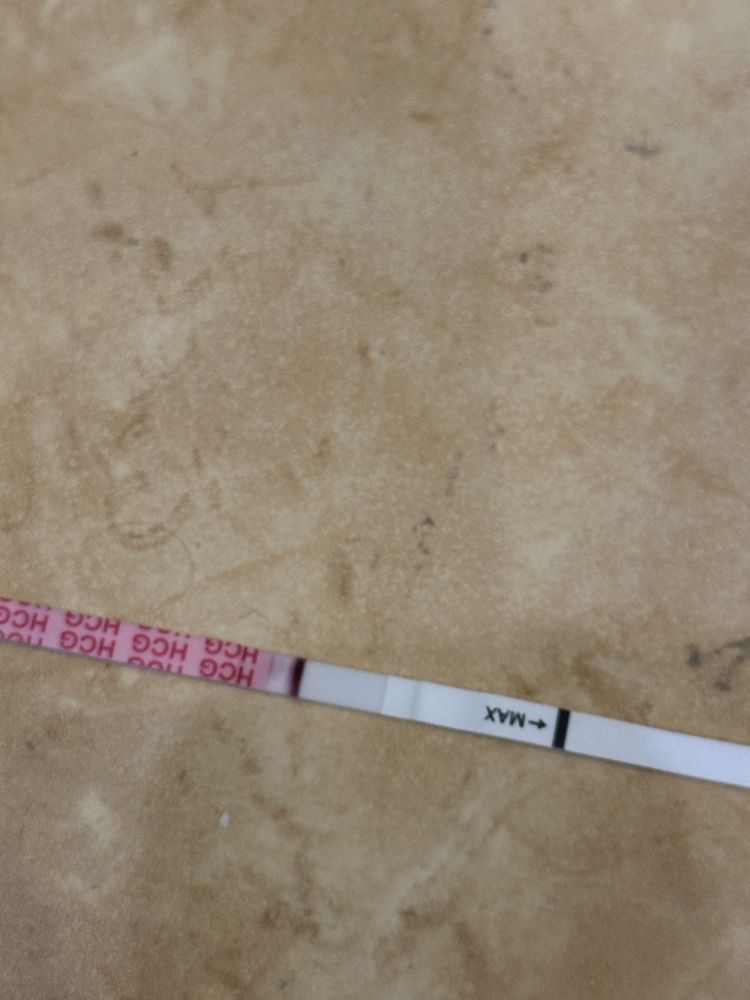

Овуляция была или ещё будет?

Как думаете, овуляция была уже? Если да, то на какой дц?

1 февраля тест положительный,значит была 1-3 февраля

Наталья, а почему тогда не снижается ЛГ, не знаете? На сколько я знаю, то должно снижаться.. вот Фемометр мне показывает сегодня пик🫠

Наталья, от первого тоже говорил пик, и тоже 200%🤔

Наталья, поэтому я и думаю что странный цикл, странные тесты, графики - не перерос ли фоликул в кисту. А то такое ощущение, что овуляция вот-вот наступит и не наступает (по тестах и графику). А вот симптомы все второй фазы (выделения, боль в груди, аппетит, усталость, головная боль)

про лг вот читала, поэтому такое ощущение, что фолликул перерос в кисту🥺

раньше на 17-19 дц ловила пик

Если у женщины исходно повышен уровень ЛГ, тест может оказаться положительным. Такая ситуация наблюдается у пациенток с преждевременной недостаточностью яичников, а также в позднем репродуктивном возрасте, когда уровни гонадотропинов (ФСГ и ЛГ) изначально повышены.

Бывают ситуации, когда повышение уровня ЛГ начинается, но оказывается недостаточным. Овуляции не происходит, а преовуляторный фолликул преобразуется в фолликулярную кисту.

А ещё у девушки на форуме тесты на овуляцию были все время положительные и она оказалась беременной